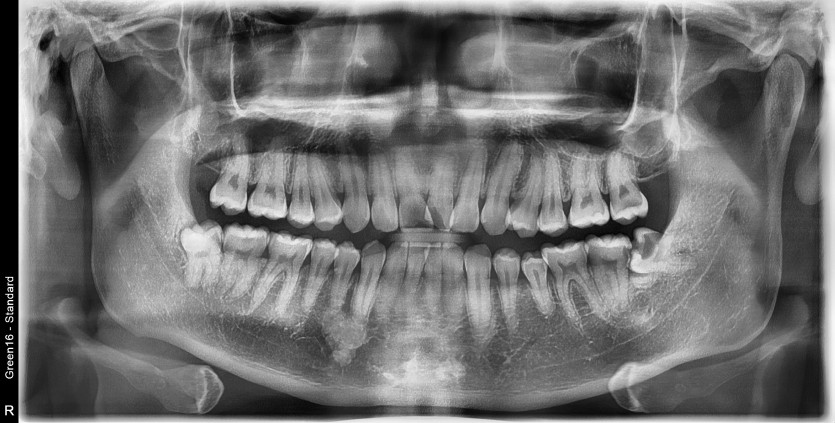

#38 사랑니 발치

구강 외과 전문의가 당일 발치했습니다.